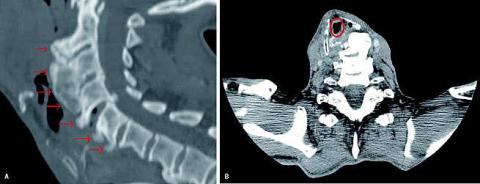

En 62-årig mand blev indlagt til operation for aortaaneurisme. Patienten havde haft let synkebesvær i ca. et år, men ellers ingen øre-næse-hals-gener. Primær intubation var vanskeliggjort af dislokation af trachea. Ved fiberskopi blev der fundet en tumorproces i hypopharynx, en biopsi viste knogle. Efter få dage blev patienten genindlagt med tiltagende stridor, konfusion samt hallucinationer, og der blev foretaget akut trakeostomi. En skanning viste udtalt osteofytdannelse anteriort og i mindre omfang posteriort på columna i C2-C7 (A ). Trachea blev forskudt lateralt (B ). I samarbejde med neurokirurgisk afdeling blev der afmejslet osteofytter. Herefter kunne larynx mobiliseres og optimalt placeres. Postoperativt var der ingen respiratoriske problemer, og trakealkanylen kunne seponeres inden udskrivelsen.

Hypertrofiske anteriorcervikale osteofytter (HACO) er med en incidens på 12-30% et almindeligt fund hos den ældre befolkning [1]. Det er ofte associeret med kompression af øsofagus og larynx [2]. Dysfagi ses hos op til 28% af patienterne, men derudover ses kliniske symptomer sjældent [3]. HACO optræder i degenerativ diskussygdom, accelereret aldringsproces og Forestiers sygdom [3].